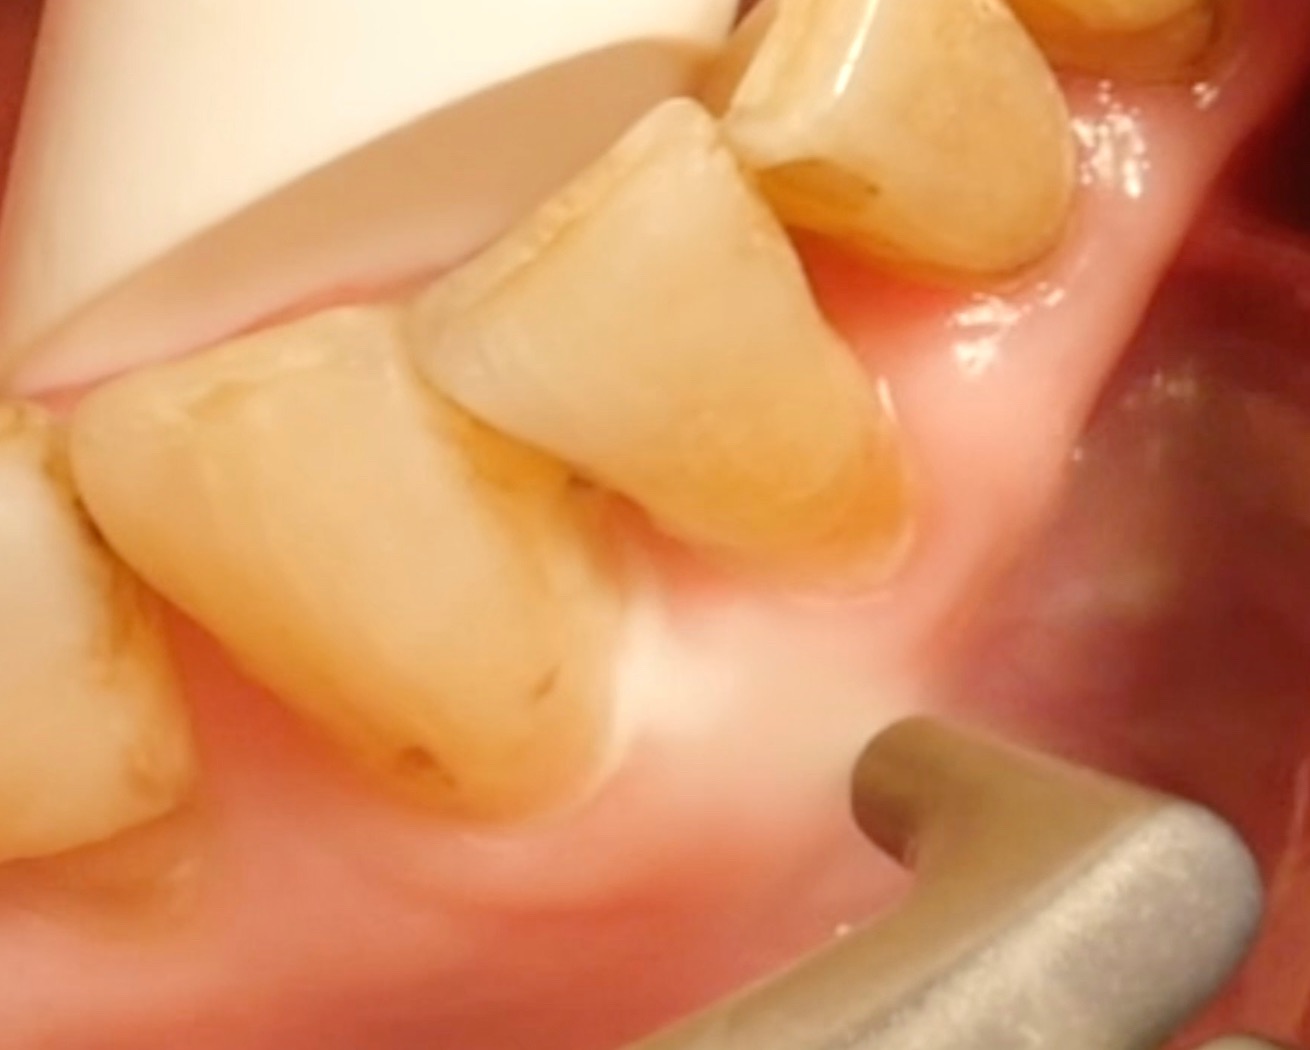

• For pocket probing depths of ≤ 4 mm and of 5–9 mm, removing biofilm with an air polisher is more effective and quicker than conventional methods; however, the clinical outcome is comparable, and no method is clearly superior.

• However, it is essential to note that air-polishing devices cannot ablate deposits of tartar and calculus; here, a combination of (ultra)sonic devices and/or hand instruments must be used.